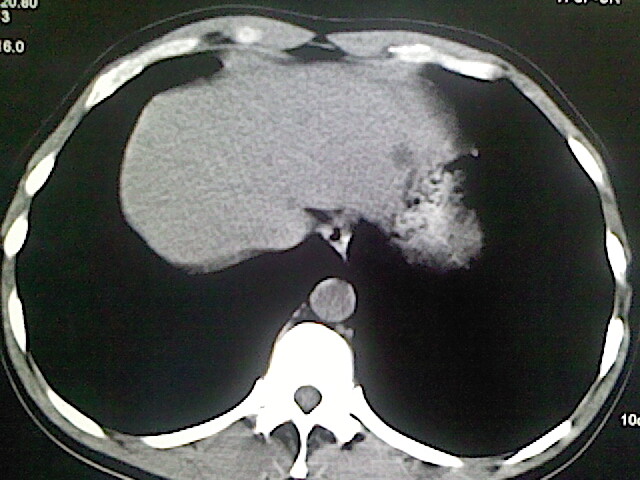

以下是引用卜一在2009-3-14 9:49:00的发言:[br]胆囊萎缩,胆囊壁不规则增厚,内部结构模糊,增强明显强化。另:肝左叶外侧段肝囊肿。支持:慢性胆囊炎!高度可疑:胆囊癌!

以下是引用余辉在2009-3-14 8:48:00的发言:[br]1)慢性胆囊炎。2)肝左叶外侧段肝囊肿。3)脂肪肝。[br]支持,胆囊萎缩,密度增高,不知b超具体有何提示,钙胆汁?结石?

以下是引用jiangjing在2009-3-14 10:18:00的发言:[br]1)慢性胆囊炎。2)肝左叶外侧段肝囊肿。3)脂肪肝。4.】建议行肝功能检查